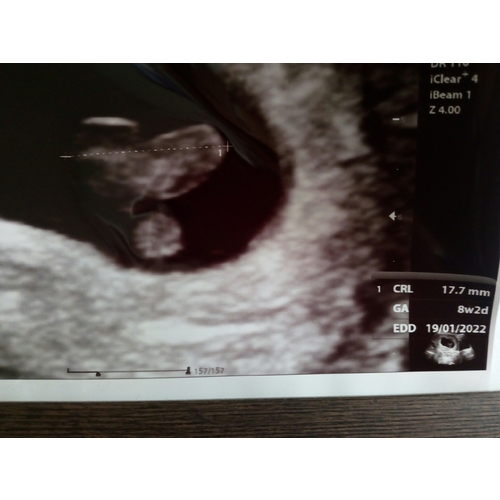

Wel heeeel blij en een geruststelling dat het met het garnaaltje helemaal goed gaat. Alles wat er nu zichtbaar zou kunnen zijn zit erop en eraan en het hartje klopt heel duidelijk ❤